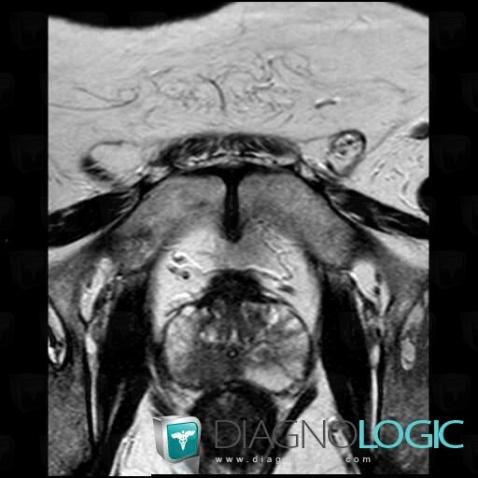

Prostate cancer, Prostate, MRI

Here is the specific information in the key image above:

- Diagnosis Prostate cancer, Location(s) Prostate, with gamuts T2 WI hypointense prostatic lesion